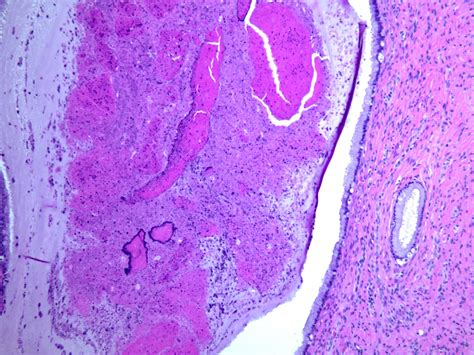

The most common type of cyst on cervix is known as a Nabothian cyst. These are small, benign lumps that form on the surface of the cervix. They occur when the glands that produce cervical mucus become obstructed by skin cells or inflammation, causing the mucus to build up and form a small, fluid-filled bump.

The cervix is covered in different types of cells. In the area known as the transformation zone, squamous cells (skin-like cells) can grow over the openings of the mucus-producing columnar glands. When this happens, the gland continues to secrete mucus, but because the exit is blocked, it gets trapped, creating a smooth, white or yellow bump that can feel firm to the touch.

Because they are rarely symptomatic, most cysts are detected incidentally. Your gynecologist will typically identify a cyst on cervix during a standard pelvic exam. The doctor can usually recognize the smooth, firm, rounded appearance of a Nabothian cyst by sight alone.

• Colposcopy: This involves using a specialized magnifying instrument to look closely at the cervix, allowing the doctor to get a better view of the tissue.

• Biopsy: Although rare for simple cysts, a biopsy may be performed if the growth appears unusual, to ensure it is not related to cervical dysplasia or other abnormalities.